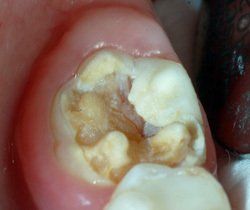

Bei Substanzdefekten, Karies und starker Empfindlichkeit sind Compositefüllungen und eventuell stützende Edelstahlbänder die beste Versorgung. Hier ein Fall aus unserer Praxis:

Molarenband am Modell zur Besseren Vorstellung